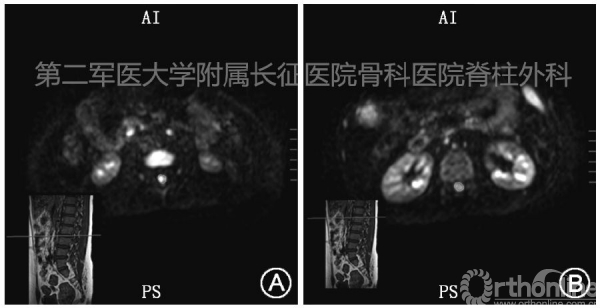

1.磁共振弥散张量成像(DTI):常规MRI的T1、T2加权在脊髓损伤时可显示脊髓信号改变,但对于TCS患者脊髓的轴性牵拉损伤无法显示或量化分析,本研究运用Cui等报道的脊髓弥散张量成像技术,计算反应脊髓受牵拉情况和损伤范围值(orientation entropy,0E)(图1) 。

图1 腰椎磁共振弥散张量成像在不同层面对脊髓的0E值进行计算,图中所圈部分即为该节段脊髓的范围,使用0E值判断受累脊髓节段及范围。A中脊髓0E为0.98; B中脊髓0E为0.75,0E值高于0.8则认为该段脊髓受到牵拉损伤(正常腰段脊髓基准值0.72±0.05)